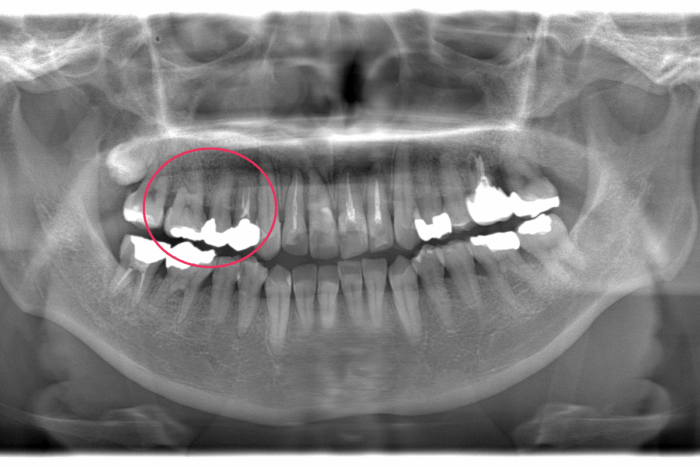

患者さま:40代女性/右上4・5・6番にメタルブリッジ

主訴:歯並びのガタガタが気になる

年齢と銀歯がたくさん入っているので、矯正できるか気にされていました。ブリッジの部分の歯根状態に問題がなかったのでブリッジはそのまま、マウスピース矯正装置(インビザライン)で矯正治療を行いました。

- 【症例詳細】

- 主訴:ガタガタが気になる

- 診断名:叢生

- 初診時年齢:49歳

- 使用装置:マウスピース矯正装置(インビザライン)

- 抜歯部位:なし

- 治療期間:1年2ヶ月

- 費用:¥865,000(税込¥951,500)

- リスク・副作用:痛み、歯根吸収、歯肉退縮、むし歯、後戻り